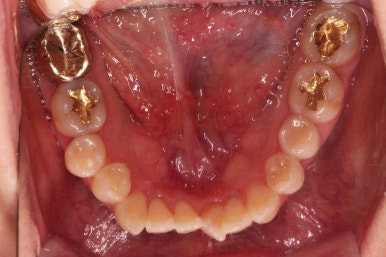

1. 초진

부산개방교합 키다리아저씨치과에 처음 내원 시 입안의 모습입니다.

전반적으로 치열이 삐뚤고요.

앞니쪽이 다물어지지 않는 개방교합(오픈바이트, open bite) 을 보였습니다.

어금니 맞물림을 보면 앵글씨 2급 부정교합 양상이어서 위아랫니가 모두 1대1로 부딪히고 있는 상태였습니다.